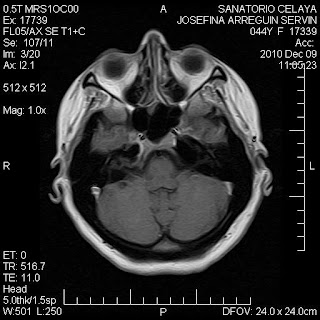

En esta otra imagen que ubica al tálamo, una imagen que a priori parece tumor (si se ven las demás imágenes esta aparece muy redondeada, con deformación del ventrículo lateral y con cierto "efecto de masa"), la espectroscopia aquí muestra una reducción de la colina.